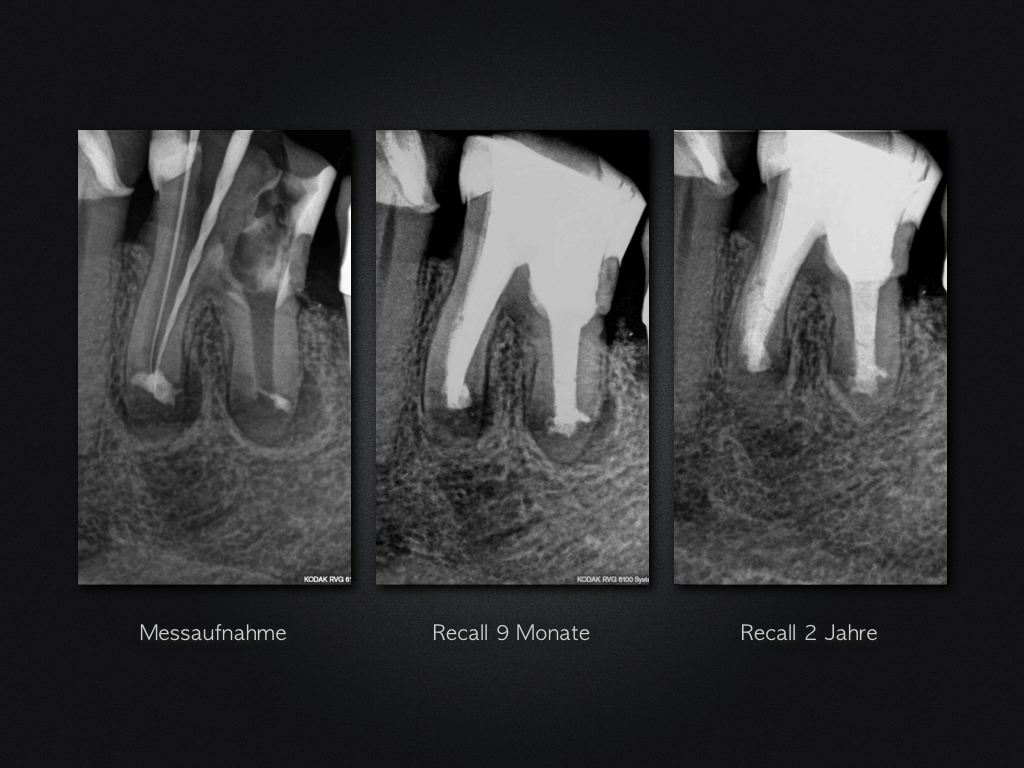

36D.005

WSR ohne WF